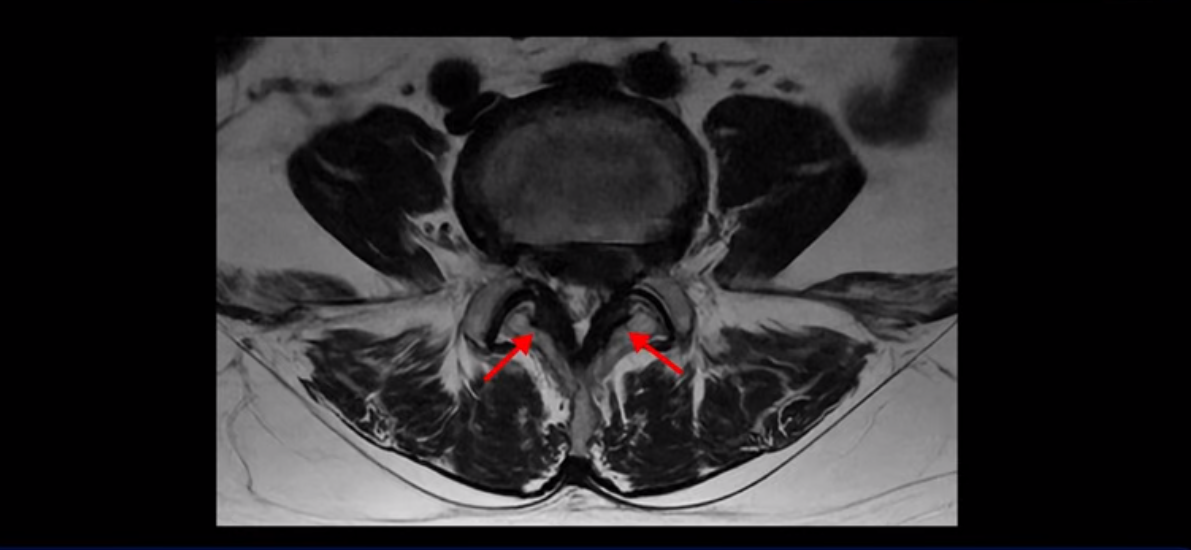

단면을 보면 디스크 수핵은 왼쪽으로 심하게 밀려 나와 있고

좌우 뒤쪽에는 황색 인대가 두꺼워져 있습니다.

앞에서는 디스크 수핵이 신경 공간으로 침범하고 뒤에서는 두꺼워진 인대가 신경 공간을 좁히고 있습니다.

이렇게 신경 공간이 좁아진 것을 협착이라고 합니다. 왼쪽으로 신경 구멍이 더 좁아져 있으니까 처음에는 왼쪽 엉덩이와 다리가 아팠는데 몇 년 동안 주사 맞으면서 버티다 보니까 오른쪽 다리까지 아프게 됩니다. 결국 양쪽 다리가 너무 아파서 5분 걷기도 힘들어지게 됩니다.